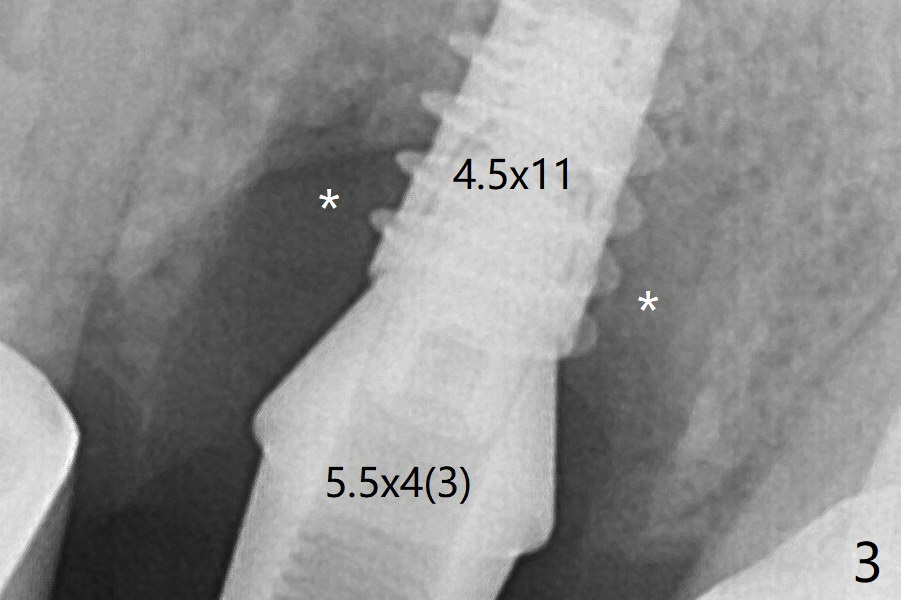

左上6腭侧退缩牙龈(图一:箭头)深部没有骨壁(图二:*),4.5x11毫米植体周围缺损(图三:*)由粘性骨粉(皮质骨,图四:*)填入。术后四个月骨粉形态接近原位骨(图八),但是腭侧软硬组织仍有缺损,炎症。